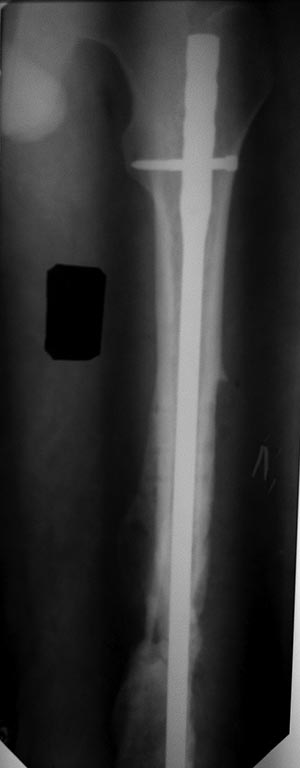

Уважаемые коллеги! Помогите определиться с тактикой лечения у молодого

пациента.

Молодой парень, 25лет. Травму получил в ноябре 2012 года, ДТП.Оперирован

в сельской больнице, остеосинтез перелома бедренной кости пластиной и

АВФ на голень с этой стороны, наложена гипсовая повязка коксит на 3

месяца. В момент госпитализации разгибательная контрактура коленного

сустава (движения в коленном суставе сгибание 10 градусов) 02.07.2013

произведена операция - удаление металоконструкции с бедренной кости,

костная аутопластика( из подвздошной кости) и БИОС бедренной кости

универсальным гвоздем ChM. ЭОПа у нас нет, пользуемся переносным

рентгенапаратом. Как быть с ложным суставом голени?